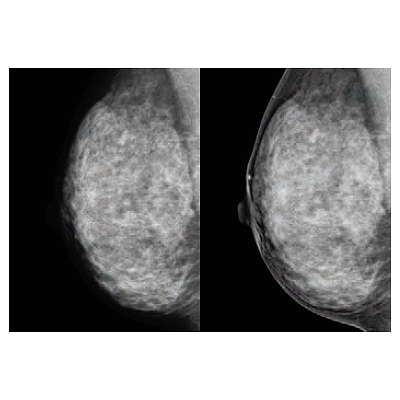

●読影しやすい画像で、日本人女性に多い高濃度乳房にしっかり対応。検査の質が向上します。